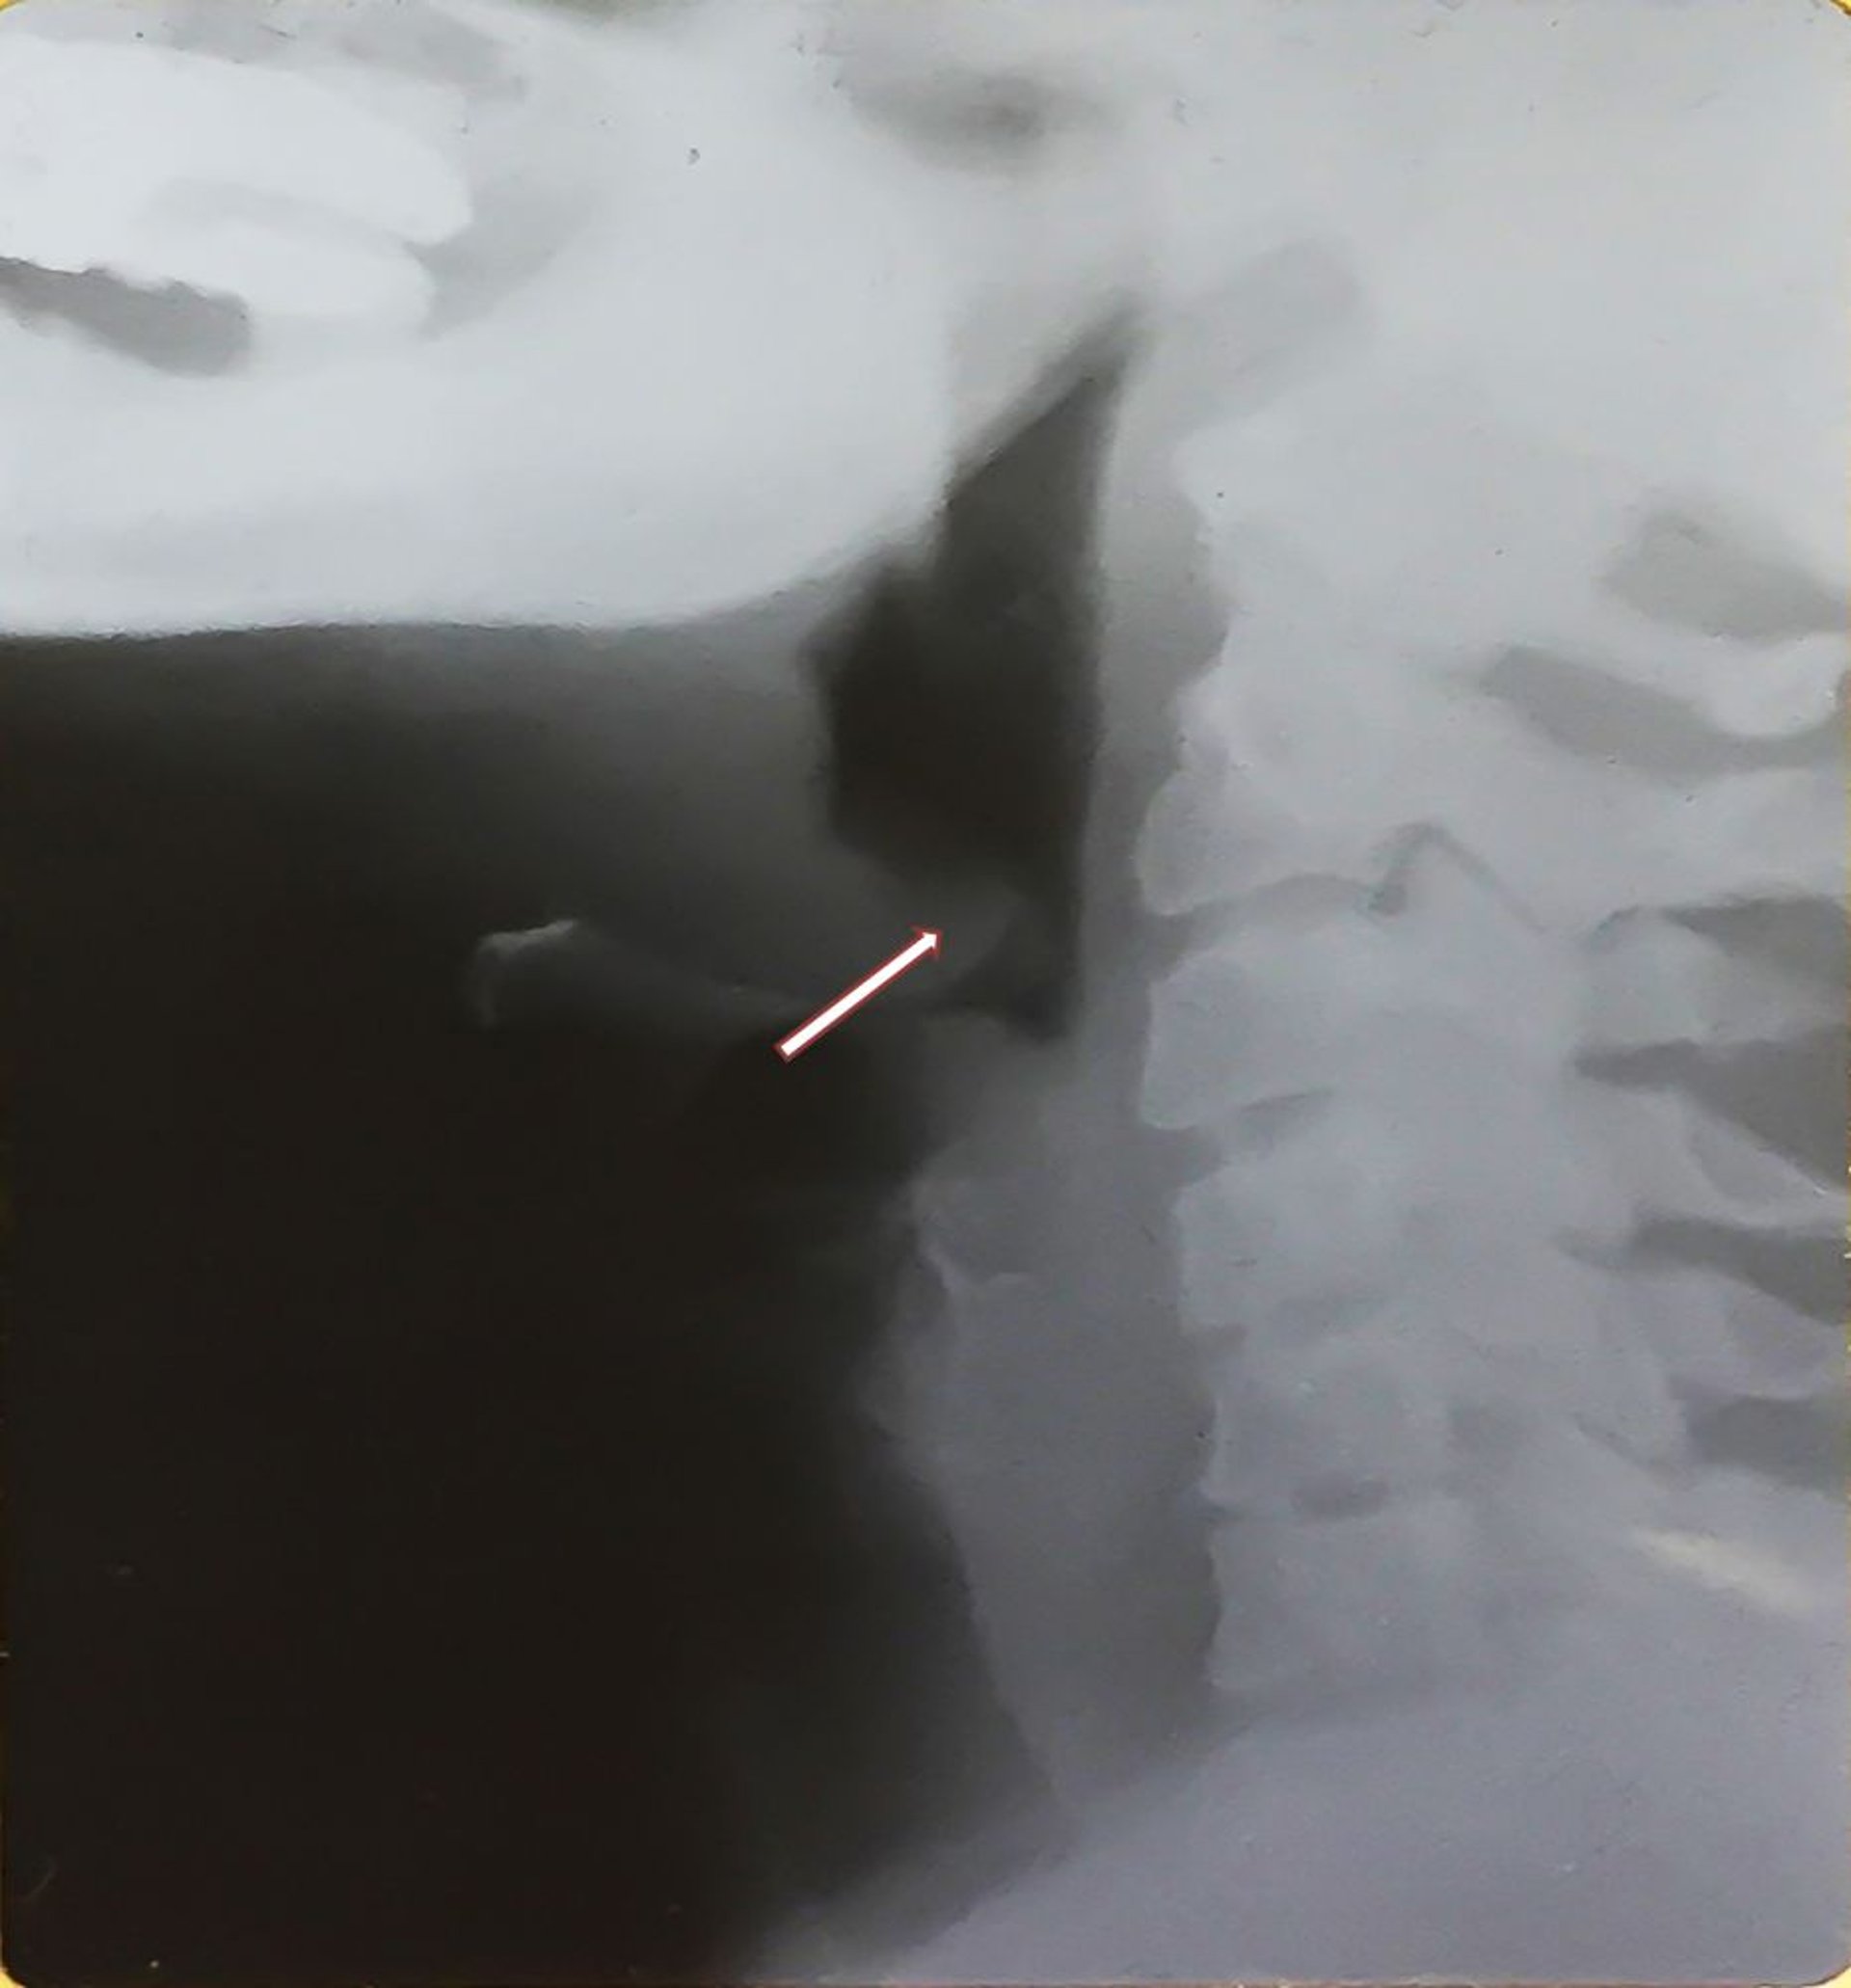

Viêm nắp thanh quản (người lớn)

Phim chụp X-quang này cho thấy nắp thanh quản phì đại (dấu hiệu ngón tay cái – xem mũi tên) đặc trưng của viêm nắp thanh quản và sưng phồng hạ họng. Lưu ý nắp thanh quản bị di lệch ra sau, dày lên.

Hình ảnh do bác sĩ Clarence T. Sasaki cung cấp.